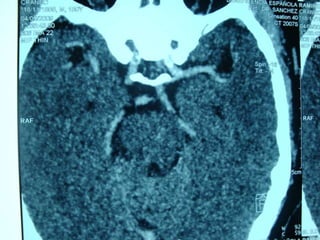

 Trombolisis intra-arterial y rescate vascular

en el infarto cerebral agudo DENTRO DE 6

HRS

 Trombolisis intravenosa por Medicos

expertos en terapia endovascular ,

NEUROLOGOS.

 PROACT

 PROACT II

 TROMBECTOMIA ENDOVASCULAR

 MERCI

 MR RESCUE

 EPAR

 Angioplastia